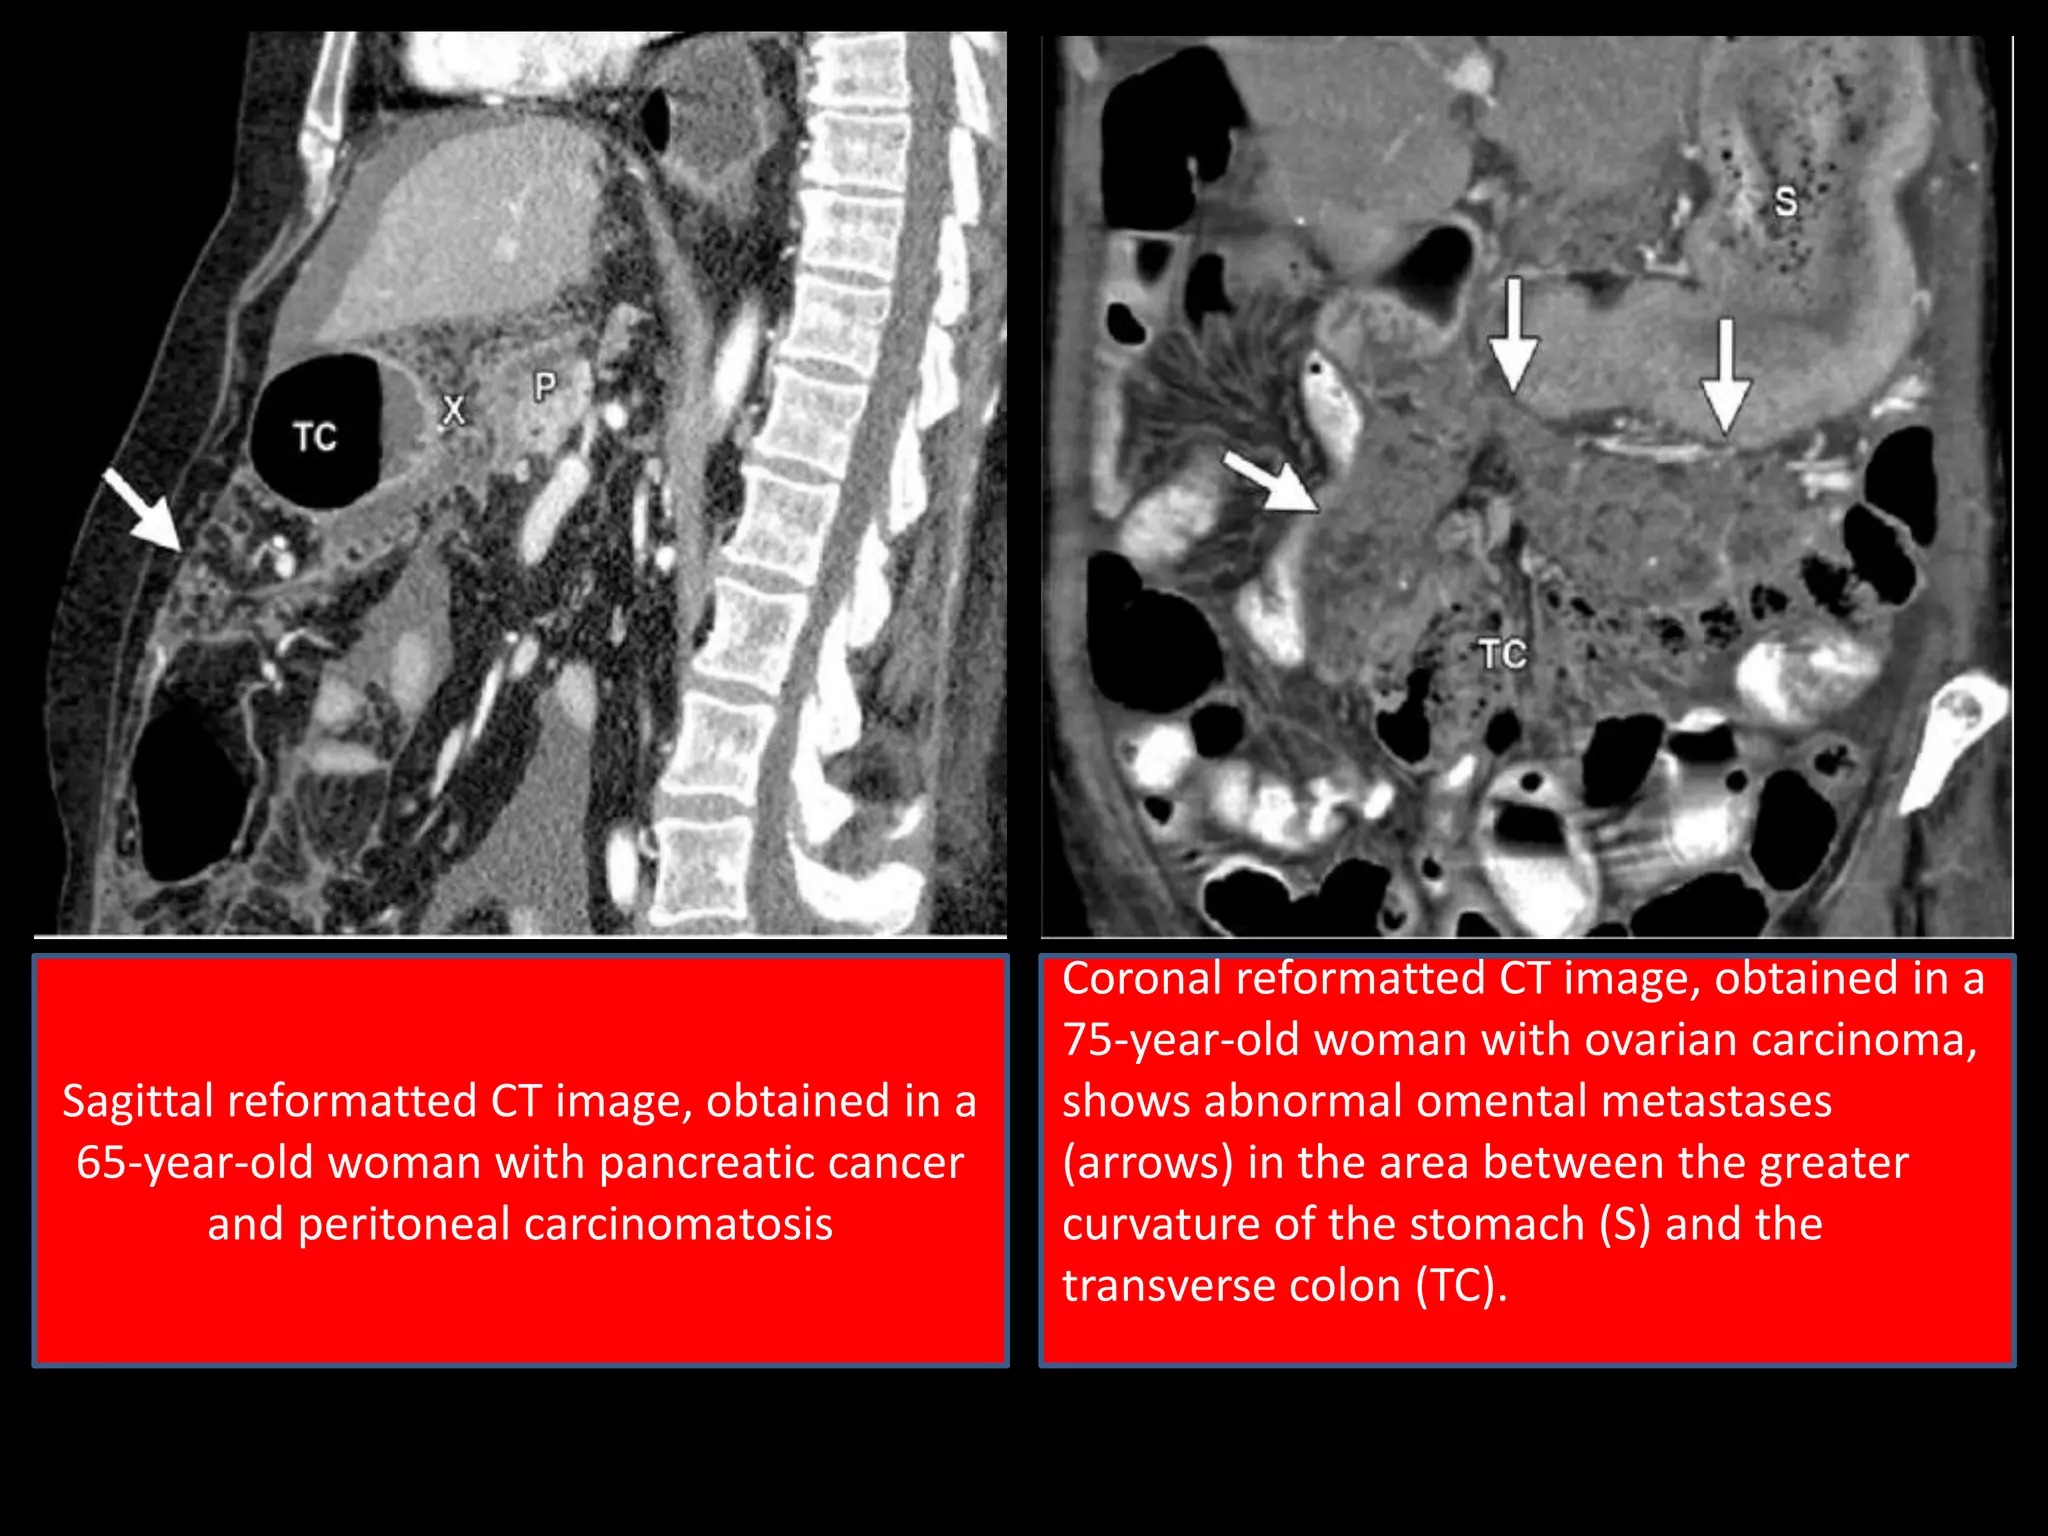

Sagittal reformatted CT image, obtained in a

65-year-old woman with pancreatic cancer

and peritoneal carcinomatosis

Coronal reformatted CT image, obtained in a

75-year-old woman with ovarian carcinoma,

shows abnormal omental metastases

(arrows) in the area between the greater

curvature of the stomach (S) and the

transverse colon (TC).